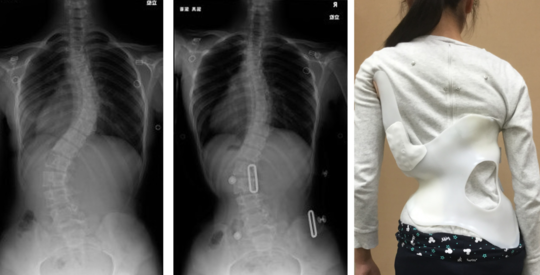

改善例1

改善例2

シュロス法の ゲンシンゲン装具を装着した画像です。カーブの角度が明らかに改善していることがわかります。

カーブタイプによっては改善例2のようにショートタイプの装具でも十分に矯正が可能です。

従来の側弯症治療では手術以外にカーブの変形を改善することは難しいと言われていますが、このゲンシンゲン装具とシュロス法の運動療法を併用することで側弯の改善を可能にしています。